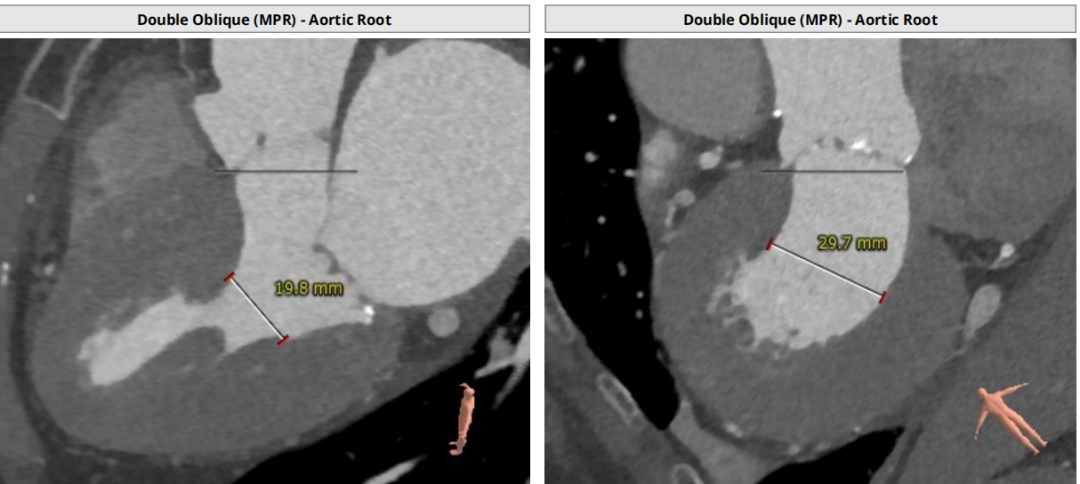

术前CT评估:

瓣环平均直径:25.2mm,左室流出道平均直径:25.5mm;

升主动脉(未见)明显扩张,心脏角度:47°;

左冠高度:12.1mm,右冠高度:16.1mm。

Annulus:25.2mm

LVOT:25.5mm

Sinus:22.1mm*32.6mm STJ:30.3mm

升主:34mm*34.7mm 主动脉成角:47°

钙化积分:272

手术策略

患者主动脉瓣呈功能性型二叶瓣,轻度钙化,法式窦结构不大,双冠高度可,升主动脉未见明显增宽,心脏角度约47°,心肌肥厚,主动脉弓部走形平缓。

选用23mm球囊进行预扩张,通过造影观察,主动脉瓣重度狭窄,预期病人耐受球囊扩张后的反流。考虑瓣环25.2mm的直径、左室流出道25.5mm的直径、钙化分布等因素,因此判断瓣环结构对瓣膜位置要求极高,有较高风险发生瓣周漏,通过FEops技术进行综合评估后,考虑选用L29型号瓣膜,并采取稍高位释放。